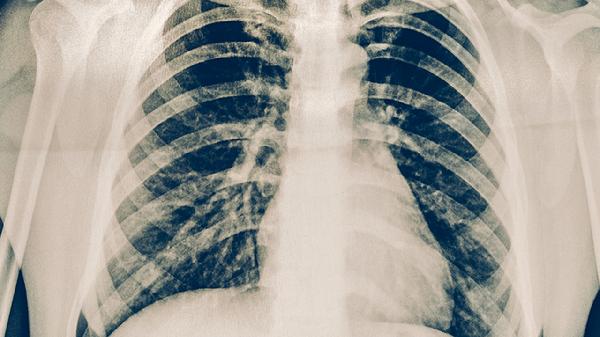

慢性阻塞性肺疾病、支气管哮喘等患者呼吸道防御功能受损,支原体感染后易发展为持续性咳嗽或喘息加重。部分患者可能合并胸腔积液或肺外表现如皮疹、关节炎等。